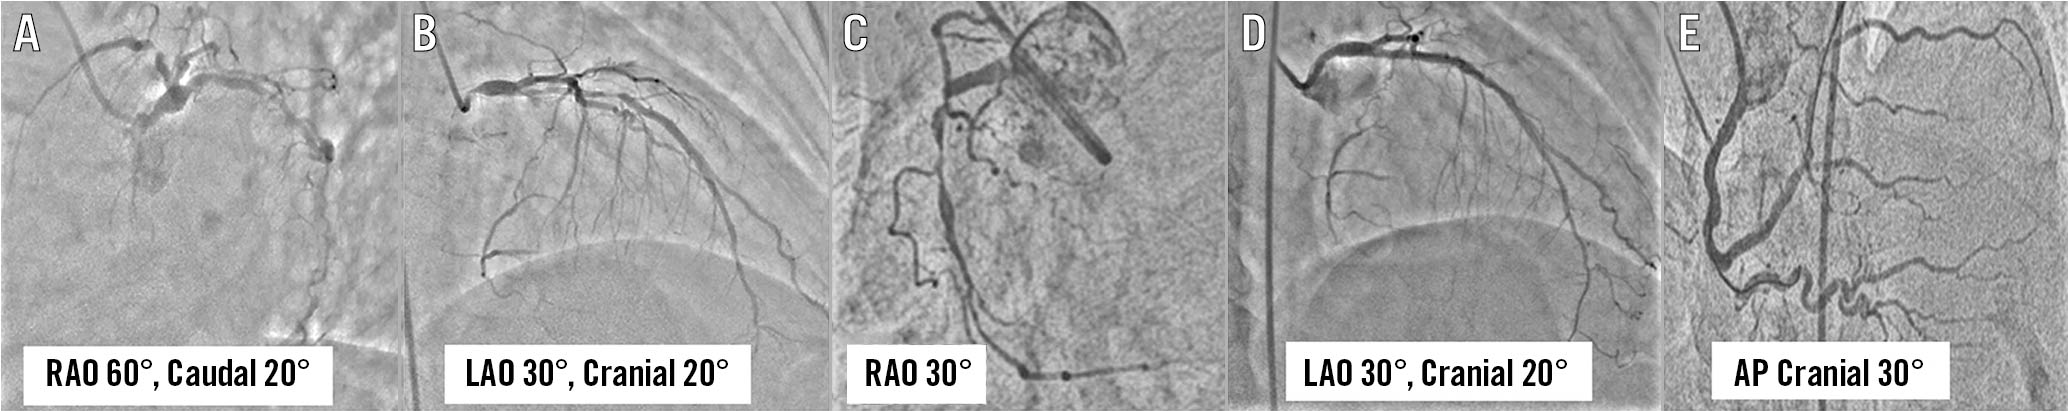

Figure 3. Coronary angiogram using the “horizontal sweep reverse” display in Case 2. Coronary angiogram of left coronary artery in RAO 60°, caudal 20° view (A) and left anterior oblique (LAO) 30°, cranial 20° view (B) showed diffuse disease of proximal to mid-left anterior descending (LAD) artery. Coronary angiogram of the right coronary artery (RCA) in right anterior oblique (RAO) 30° view showed diffuse disease of proximal to distal RCA (C). A repeat angiogram following successful stenting of LAD in LAO 30°, cranial 20° view (D) and RCA in antero-posterior (AP) cranial 30° view (E).